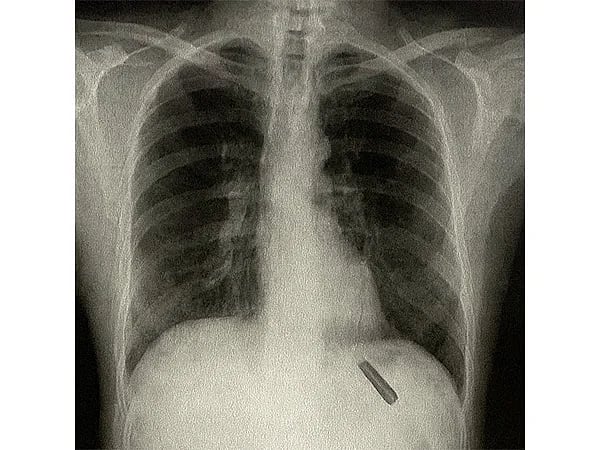

இதையடுத்து, மருத்துவர்கள் மேற்கொண்ட எக்ஸ்ரே உள்ளிட்ட பரிசோதனைகளின் மூலம், அவரது நுரையீரலின் பேனா மூடி ஒன்று சிக்கியுள்ளது தெரியவந்தது.

இந்நிலையில், மருத்துவர் சபியாசாச்சி பாய் தலைமையிலான குழுவினர், அறுவைச் சிகிச்சையின் மூலம், 26 ஆண்டுகளாக அவரது நுரையீரலில் சிக்கியிருந்த பிளாஸ்டிக் பேனா மூடியை வெற்றிகரமாக அகற்றியுள்ளனர்.